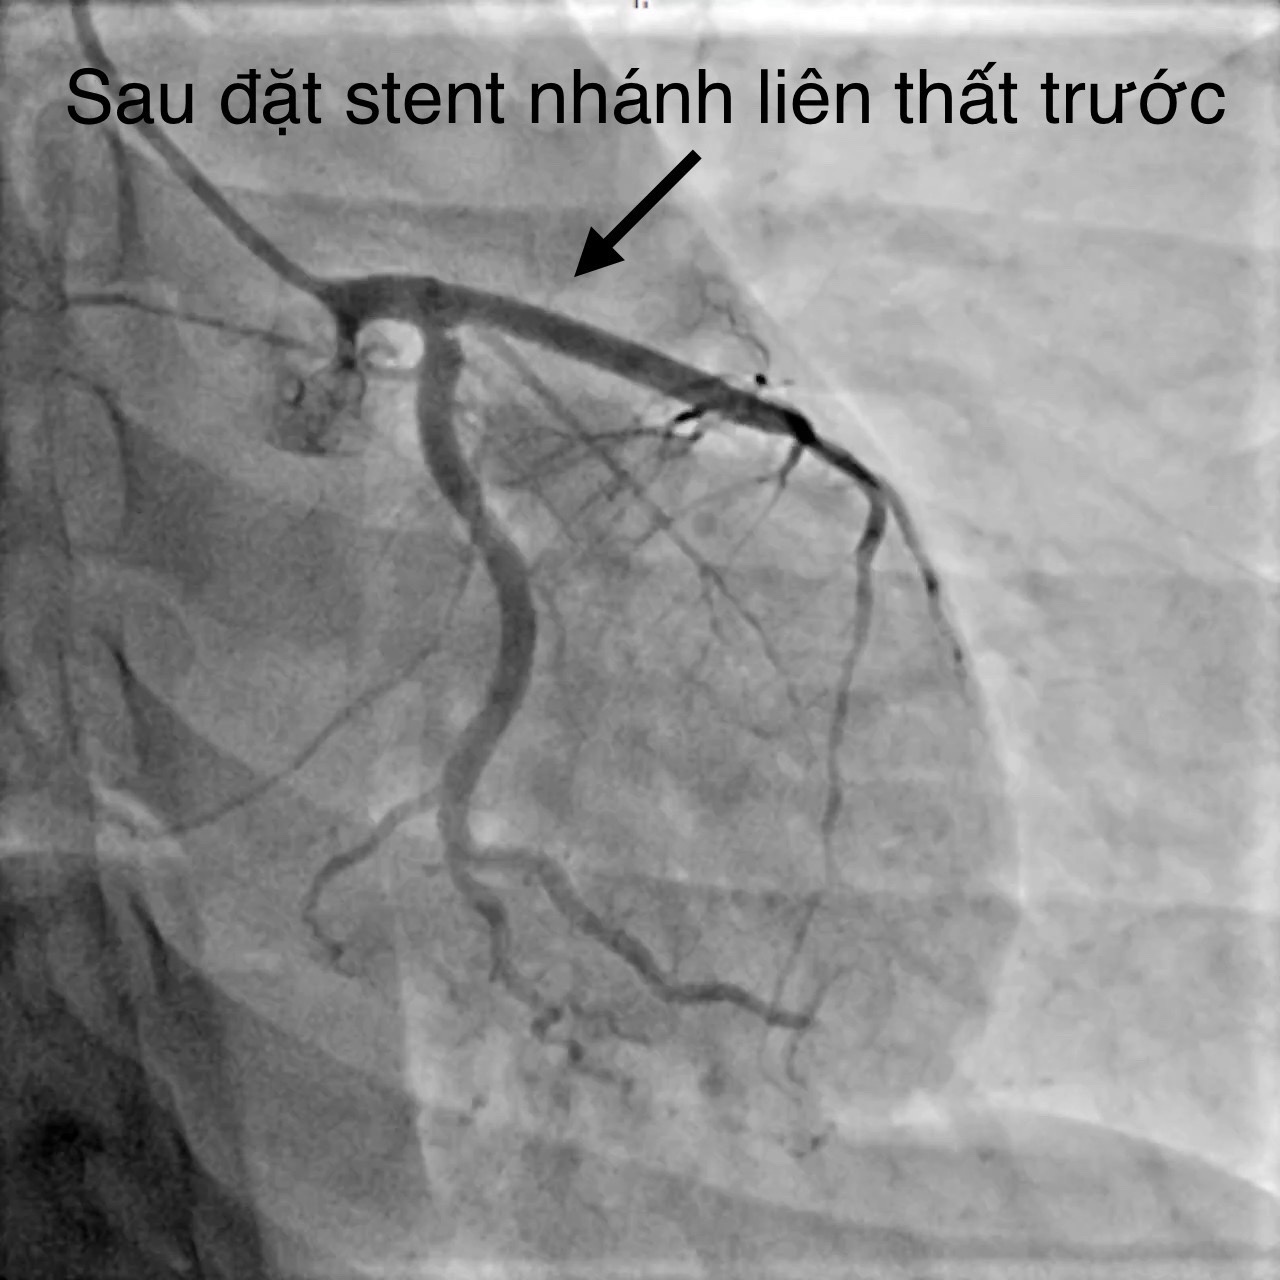

Bệnh nhân đã được hội chẩn nhiều chuyên khoa: Tim mạch can thiệp, Nội Tim mạch, Ngoại Lồng mạch máu, Ngoại thần kinh, Mắt... Bệnh nhân có chỉ định can thiệp mạch vành cấp cứu do BSCKII. Trần Văn Triệu – Phó khoa phụ trách khoa Tim mạch can thiệp thực hiện, kết quả ghi nhận tắc từ lỗ động mạch vành liên thất trước (động mạch vành trái), tổn thương dạng bóc tách. Can thiệp thành công bằng một stent phủ thuốc với thời gian 35 phút. Chụp kiểm tra dòng chảy tốt , được chuyển khoa Tim mạch can thiệp chăm sóc và điều trị.